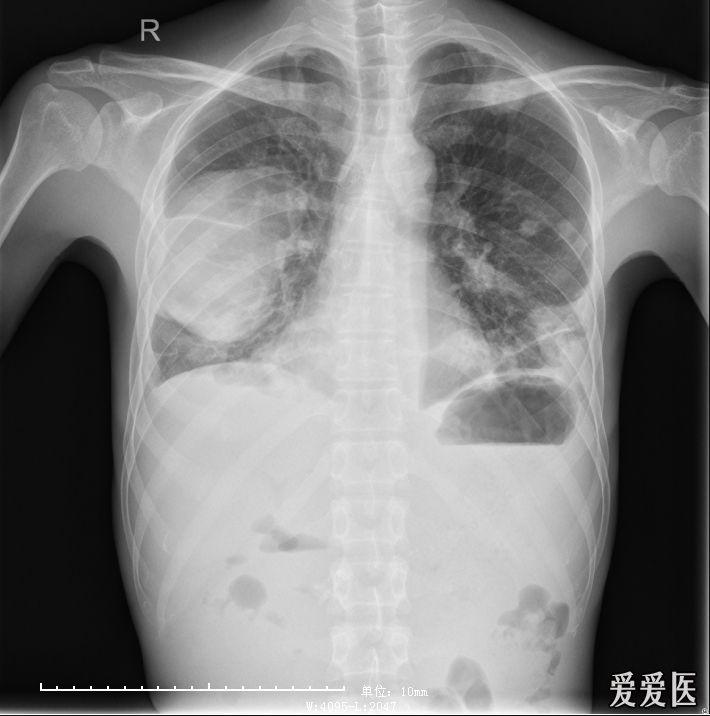

肺脓肿

肺脓肿(陶宗贵济南市人民医院影像)

慢性肺脓肿一例——陶宗贵,莱芜市医院